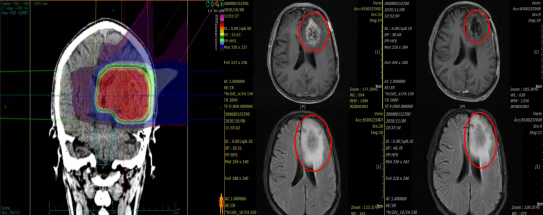

Case 3: The patient, male, 39 years old, sought medical attention due to "more than 1 year after resection of medulloblastoma." Postoperative pathological diagnosis was medulloblastoma, classic type, WHO Grade IV. The patient underwent intensity-modulated radiotherapy after surgery. A review head MRI one year later showed a space-occupying lesion in the left frontal and temporal lobes, with abnormal signals in the left medial frontal and left frontal insula, measuring 5.0 * 3.5 cm, indicating tumor recurrence. Carbon-ion radiotherapy began on October 15, 2020.

Treatment concluded on November 9, 2020. The patient's memory significantly improved, reactions became sharper, headaches completely resolved, and no discomfort occurred during treatment. A review head MRI showed that the space-occupying lesion in the left frontal and temporal lobes and the focus in the left medial frontal and left frontal insula had shrunk compared to before, measuring 4.1 * 2.7 cm, with reduced enhancement and edema.